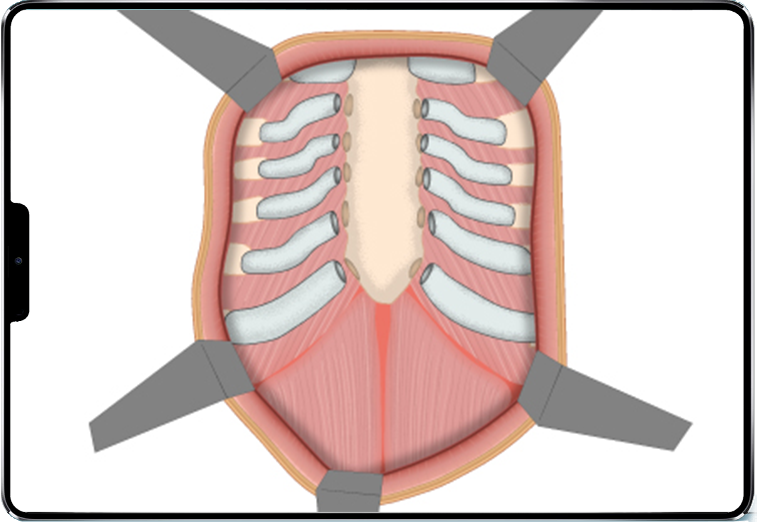

Ses caractéristiques sont les suivantes :

- incision antérieure large, souvent sous-mammaire ou médiane ;

- décollement des muscles pectoraux ;

- résection des cartilages costaux déformés et section du sternum ;

- repositionnement du sternum en position anatomique ;

- stabilisation par barres et vis d’ostéosynthèse ;

- retrait de la barre 2 à 3 ans après l’implantation.

L’opération dure en général 2 à 3 heures et l’hospitalisation entre 5 et 7 jours.